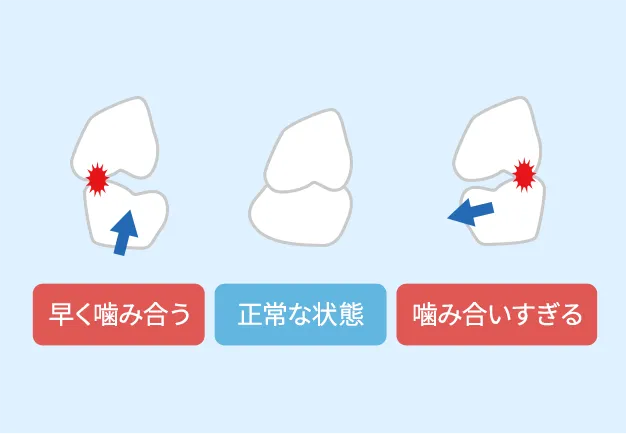

正しい位置で歯に負荷がかかる

上下に動かした時に全ての歯が同時に噛み合い、左右に動かした時に噛み合いすぎていない状態。